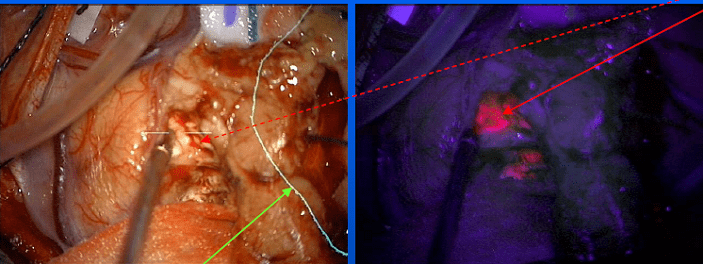

Andrew Sloan, MD, Director, Brain Tumor and Neuro-Oncology Center (BTNOC), Peter D. Cristal Chair of Neurosurgical Oncology, and Vice Chairman of Neurological Surgery, noted that new and innovative approaches to surgery often help improve the extent of resection in brain tumors. 5-Aminolevulinic acid (5-ALA) is given prior to surgery and makes the tumor fluoresce pink for more precise identification of its borders. A newer approach using cell-surface protein tyrosine phosphatase mu (Ptpu), funded by a grants to Dr. Sloan & collaborators by the Coulter Fund and the National Institute of Health (NIH), may be even more tumor specific.